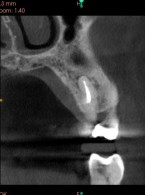

Przypadek pourazowej przyszyjkowej resorpcji zewnętrznej w zębie siecznym górnym przyśrodkowym u 15-letniego pacjenta

Zatrzymany ząb wgłobiony – opis przypadku